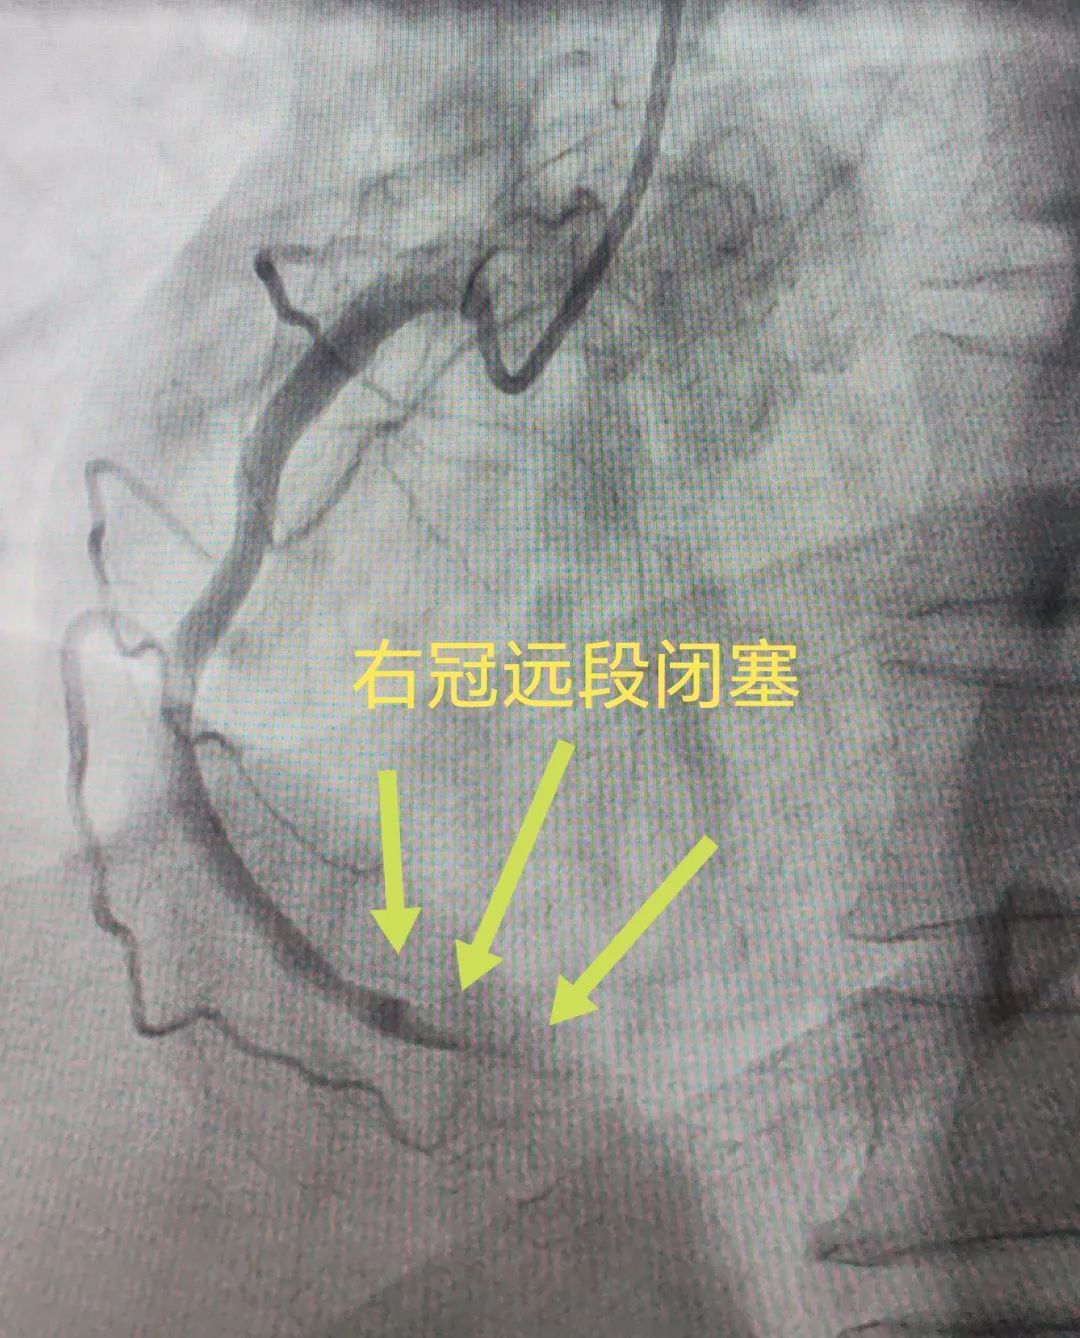

DSA 手术室早已做好手术准备,当造影导管进入冠脉时,桂伟发现,粗大的 右冠状动脉中远段完全闭塞,血栓像水泥般死死封住血管。